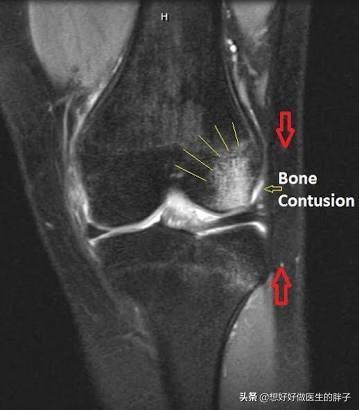

骨挫傷の1例、膝の骨挫傷です。 黒(灰色)っぽいのが骨です。 黒い骨を横切るように入っている白いイガイガの線が骨挫傷の部分です。 mriでは膝(脛骨)の横径の半分ほど亀裂が入っていますが、これでもレントゲンでは写ってきません。 今回は手術は人工関節 手術は先ず膝関節内の壊れた骨、砕けて辺りに飛び散った骨の破片を取り除き、人工関節を入れる手術です。 手術そのものの難易度はそれ程高くないのですが、むしろ怖いのは感染症です。 万一どこかに感染すれば人工関節は摘出せねば 骨挫傷とは? 骨挫傷とは、大きな外力によって骨内部の組織が損傷している状態です。 骨挫傷は、骨折と違い骨の連続性は保たれています。 そのため、簡単にいうと 骨折まで至っていない骨のケガを骨挫傷 という認識でいいと思います。 骨挫傷の場合は、レントゲンでは異常がわかることが良くないです。 そのため、MRI検査を行うと異常がわかり骨挫傷と診断されることが多いよう

3531両踵の骨挫傷の事で 更新 3月の始めにMRIで検査した結果、両踵の骨挫傷と診断されました。 左は重症で骨折と同じ状態といわれ、左だけ数週間、固定しました。 2週間後、レントゲンで経過を観察すると、だいぶマシになってるのでリハビリをVol13 骨挫傷 診断 レントゲンでは所見が見られなくても、mriで骨髄(骨の内部)に生じる異常信号像を骨挫傷と言います。mriのt1像で低信号(黒く)、stir像で高信号(白く)を呈しまず。 骨挫傷って? 骨挫傷とは骨が損傷した状態です。 膝関節や足首のケガに多く見られます。 骨のケガというと骨折を思い浮かべると思いますが骨挫傷は折れてはいません。 骨の表面もしくは内部に微細なキズができ炎症を起こした状態になります。 骨挫傷はレントゲンでは判断できず、確定診断にはMRIをとる必要があります。 そのため、ただの打撲と診断されることもありますが3週間

私たちの膝の骨の表面は、衝撃を吸収するクッションのような軟骨組織に覆われており、 大腿骨 (だいたいこつ) と 脛骨 (けいこつ) をつなぐ 膝関節 (しつかんせつ) は、軟骨があることによってスムーズな動きを維持しています。 この軟骨組織に、スポーツや外傷、事故、加齢などによって8/5/17 変形性膝関節症 による 骨挫傷 と診断されました。 骨挫傷を起こしている部位のレントゲンを見返してみても、レントゲンでは所見は認めませんね。 医師 症例 70歳代 女性 左膝痛 こちらの症例でもレントゲンでは、変形性膝関節症を疑う所見を認めていますが、骨折ははっきりしません。 ところが、MRIをみてみるとSTIRでは、大腿骨及び脛骨の近位に 著明な骨髄浮腫 を疑う高信号を認